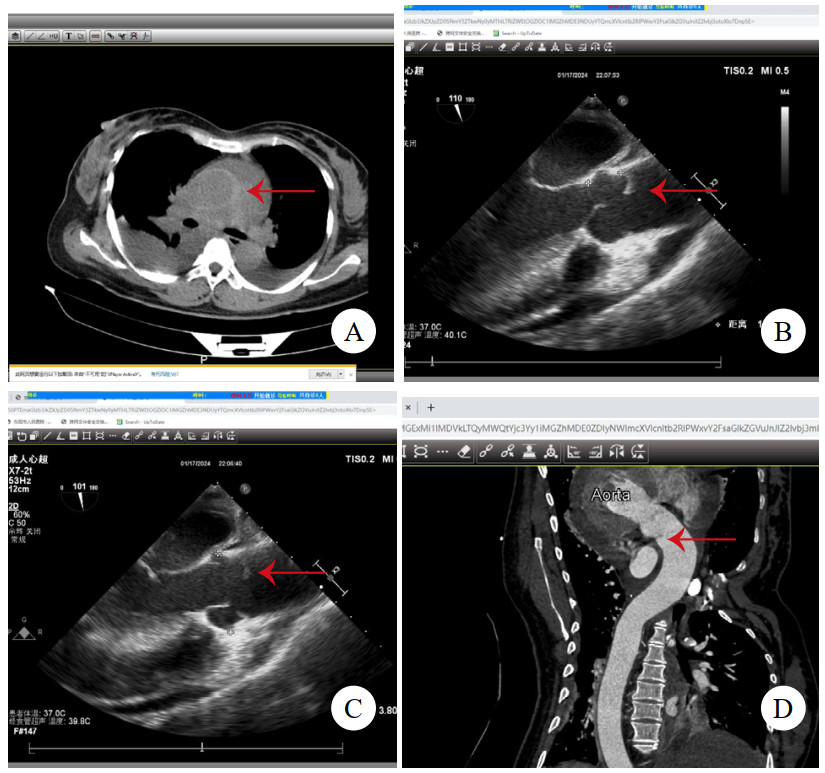

病例4,男,63岁,因“活动后胸闷、气促6年,加重1月”入院。TTE提示二尖瓣前叶A2区腱索断裂伴脱垂、重度返流,主动脉瓣重度返流,三尖瓣中度返流,左心室显著增大,左心室舒张末期直径86 mm,心功能减低,中重度肺动脉高压,升主动脉内径增宽直径43 mm。冠状动脉CTA提示双侧冠状动脉无显著病变,少量心包积液,未见主动脉根部病变(图 4A)。术前准备后,择期手术,术中见主动脉前壁窦管交界水平一长约2 cm的内膜撕裂符合LIT。仔细观察切除标本(图 4B),见内膜裂口边缘光滑,考虑为陈旧性改变。予行Bentall加二尖瓣机械瓣置换加三尖瓣成型术。术后康复顺利,规律抗凝随访1年。

| 注:A为冠状动脉CTA,未见异常;B为切除的主动脉壁,箭头示内膜裂口 图 4 例4患者CT影像及主动脉壁照片 |